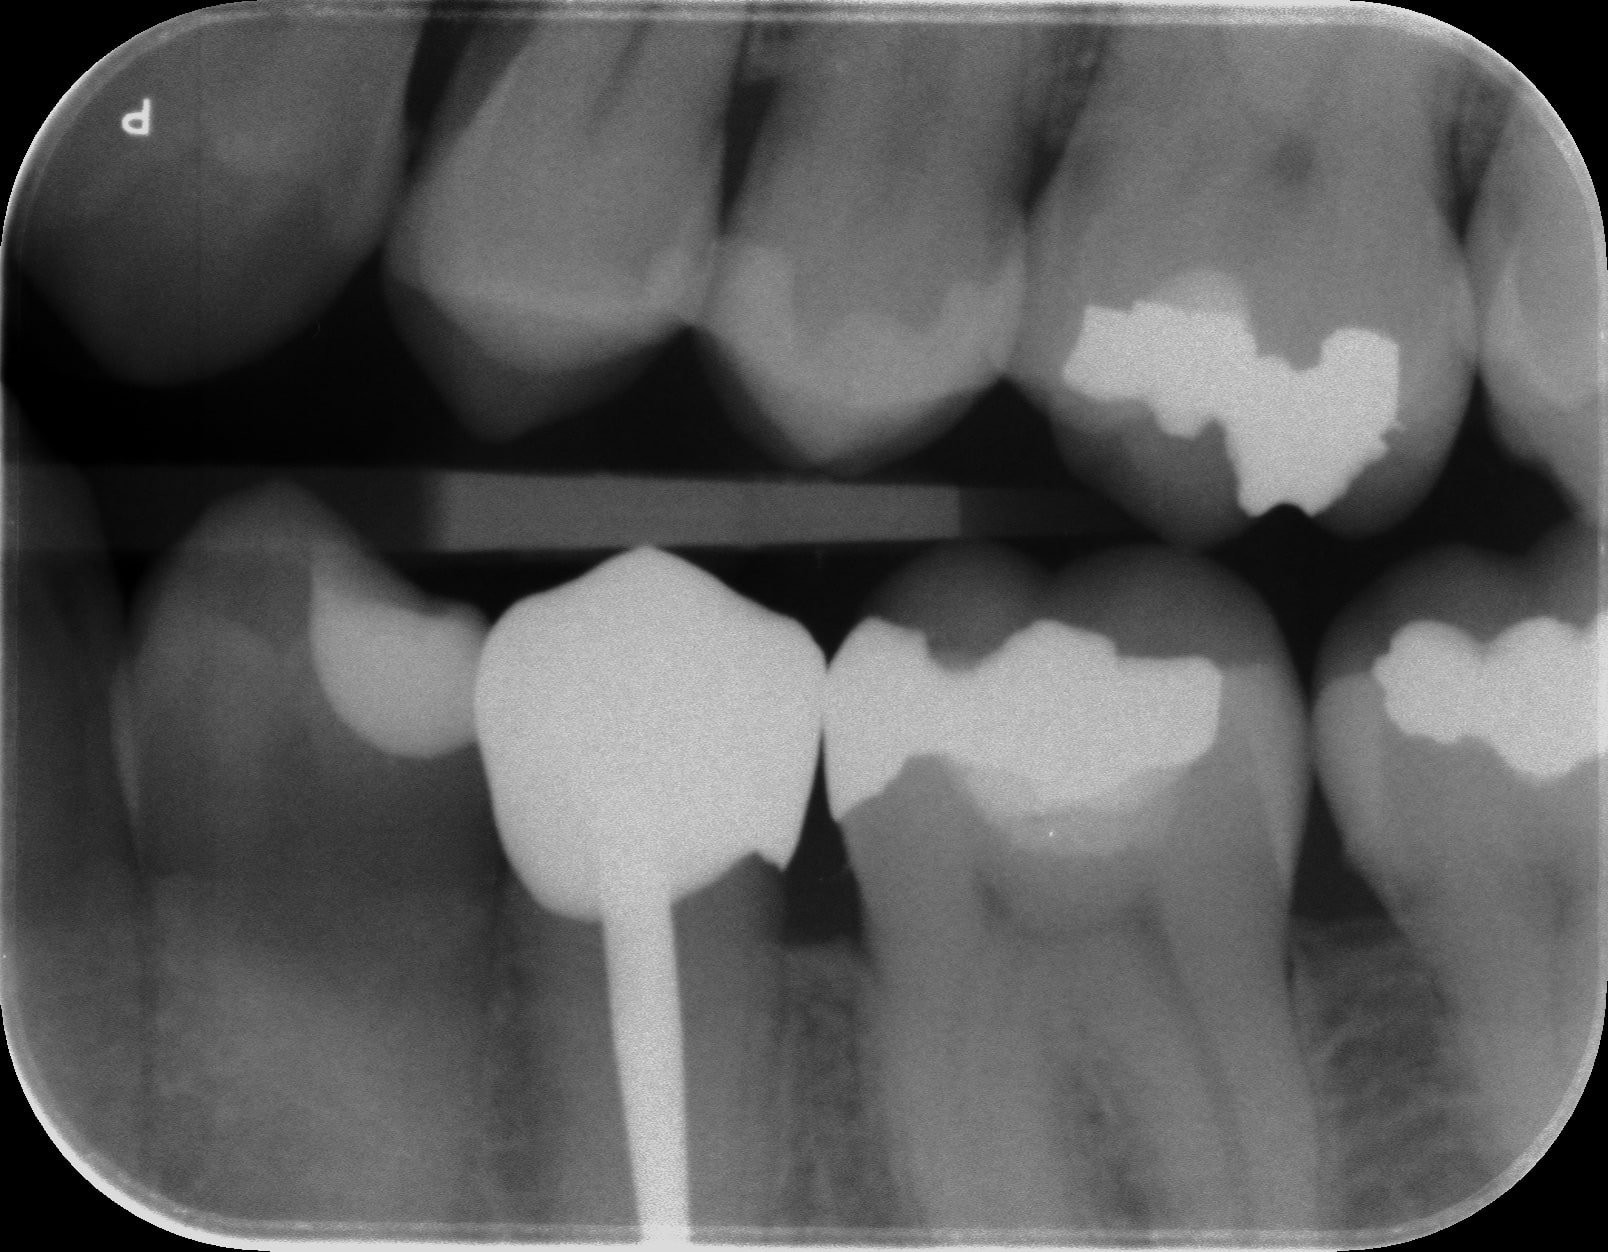

> Elle est très belle... T as une radio ?

P2 20200311 001 gxzdyg - Eugenol

Avec ces images, on comprend bien pourquoi le zircone est plus un métal qu'une céramique.